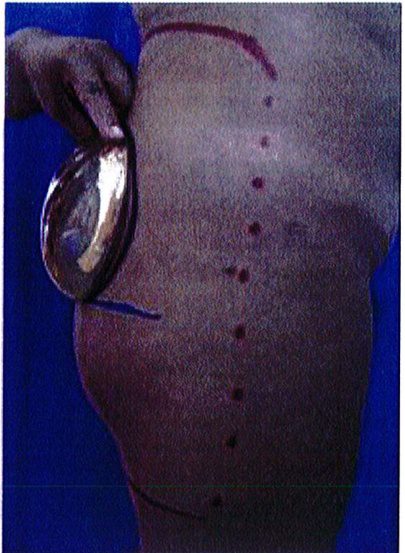

Những bệnh nhân có mào chậu rộng, khung chậu hẹp và ngắn hoặc sa hay thiếu mô mềm ở mông sẽ không phù hợp với các thủ thuật nâng mông, bất kể áp dụng ở mặt phẳng nào. Các tác giả khuyến cáo họ nên chuyển sang phương pháp ghép mỡ (Hình 2).

Hình. 2. Bệnh nhân với khung chậu quá rộng hoặc quá ngắn đều không phù hợp với implant mông.